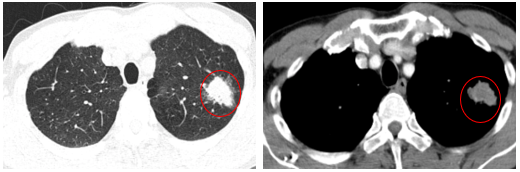

-         Chụp cắt lớp vi tính lồng ngực (06/2025): Nhu mô đỉnh phổi trái có khối tổ chức kích thước ~35x25mm, bờ không đều, có cắt cụt một số nhánh phân thùy đỉnh, ngấm thuốc mạnh không đồng nhất sau tiêm. Thuỳ trên và dưới có nốt đặc nhỏ đường kính 2mm.

Hình 1: Nhu mô đỉnh phổi trái có khối tổ chức kích thước ~35x25mm, bờ không đều, có cắt cụt một số nhánh phân thùy đỉnh, ngấm thuốc mạnh không đồng nhất sau tiêm

- Chụp cắt lớp vi tính lồng ngực (09/2025): Nhu mô thùy trên phổi trái có khối tổ chức kích thước ~39x23mm, bờ không đều, có cắt cụt một số nhánh phân thùy đỉnh, ngấm thuốc mạnh không đồng nhất sau tiêm (tăng nhẹ kích thước so với phim chụp CLVT cũ 06/2025).

Hình 6: Nhu mô thùy trên phổi trái có khối tổ chức kích thước ~39x23mm, bờ không đều

Nhận xét: Khối u phổi trên phim cắt lớp vi tính ngực (09/2025): : ~39 ×23 mm → tăng nhẹ về kích thước so với trước (35 × 25 mm), chỉ điểm u: Cyfra21-1 tăng từ 4,6 ng/ml lên 6,07 ng/ml → gợi ý bệnh ổn định Stable Disease (SD),khối u vẫn ở giai đoạn cT2N0M0. Bệnh nhân đã được hội chẩn đa chuyên khoa, có chỉ định phẫu thuật cắt thùy phổi và nạo vét hạch.